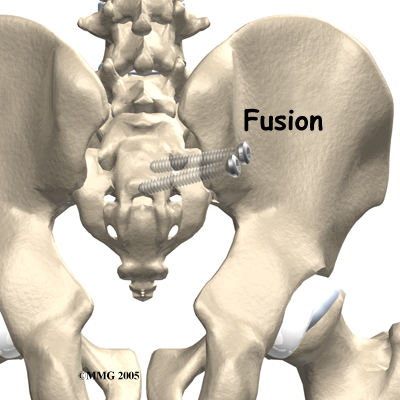

Surgery

Surgery may be considered if other treatments don't work. Surgery consists of fusing the painful SI joint. A fusion is an operation where the articular cartilage is removed from both ends of the bones forming the joint. The two bones are held together with plates and screws until the two bones grow together, or fuse, into one bone. This fusion stops any motion between the two bones and theoretically eliminates the pain from the joint.

This is a big operation and unfortunately is not always successful at relieving the pain. The operation is not commonly performed and is reserved only for use when the pain is debilitating and all other attempts at conservative treatment have failed.